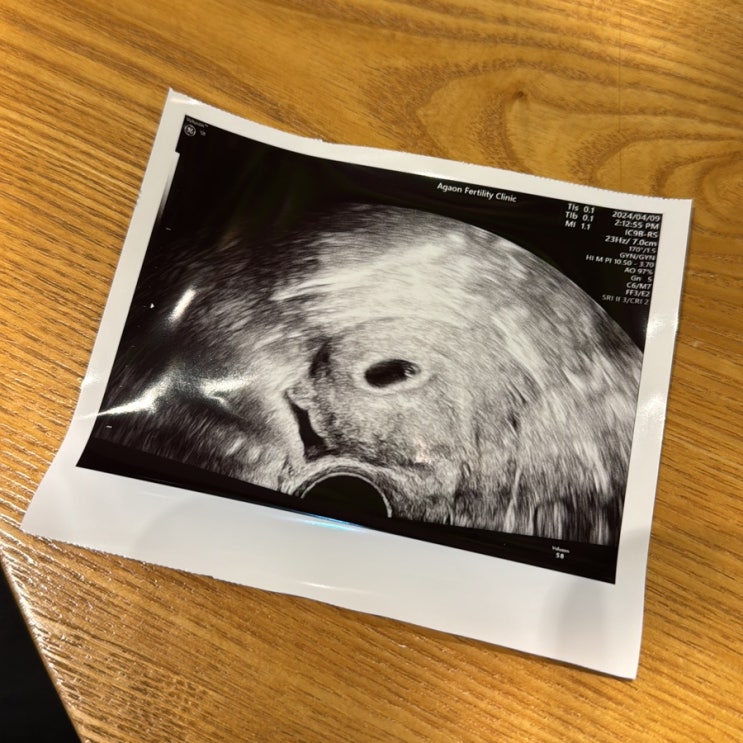

동결이식성공 증상 임밍아웃 초음파사진

너무나도 감사하게 시험관2차 성공으로 이렇게 블로그글을 써내려갈수 있게 되었는데요.. 아무래도 처음 시...

새싹이가 찾아왔어요?? 임밍아웃? 생예 전부터 흐린두줄, 임신 피검 수치, 아기집 보기전까지의 기록.

제가 사실 임신을 했답니당?? 이 글을 쓰는 오늘 기준 7주 3일차! 블로그는 검열없이 정말 솔직한 나...